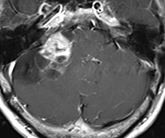

以下の画像に呈示するような脳幹や小脳を圧迫する大きい腫瘍に対しては、開頭手術が優先されます。手術中に神経刺激装置・聴性脳幹反応など電気生理学的モニタリングを併用し、1つ1つの手術操作によって神経機能を損傷していないか随時チェックしながら手術を行っており、術後後遺症の予防に努めています。